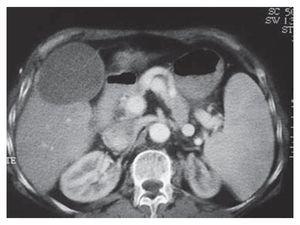

La neoplasia más común fue el hepatocarcinoma, detectado en 18 pacientes (60%) (Tabla 1). El tamaño promedio de las lesiones fue de 5.59 cm (rango 2 a 20 cm). Veintinueve pacientes (96.6%) presentabaron lesiones < 7 cm y sólo uno tuvo una lesión mayor. El número de lesiones varió de 1 a 8 (promedio 1.7). Dieciocho pacientes presentaban una lesión, nueve pacientes dos lesiones, un paciente tres lesiones, un paciente seis lesiones y ocho lesiones en un paciente. El tiempo promedio de ablación tumoral fue de 30.2 minutos (rango de 5 a 50 min). La duración del tiempo fue ajustada de acuerdo al tamaño de la lesión y con base en las modificaciones observadas mediante el uso de ultrasonido intraoperatorio. En 26 pacientes (86.6%) se realizó una sesión, en tres pacientes dos sesiones y en un paciente tres sesiones. Se llevaron a cabo 19 procedimientos por laparotomía, siete por abordaje percutáneo y cuatro por laparoscopia (Figura 1). Estos procedimientos se realizaron en forma ambulatoria en ocho pacientes y en el resto se requirió de una estancia hospitalaria de 3 días en promedio (rango de 2 a 5 días).

Figura 1. Imagen trans-operatoria en un paciente con cirrosis hepática y hepatocarcinoma